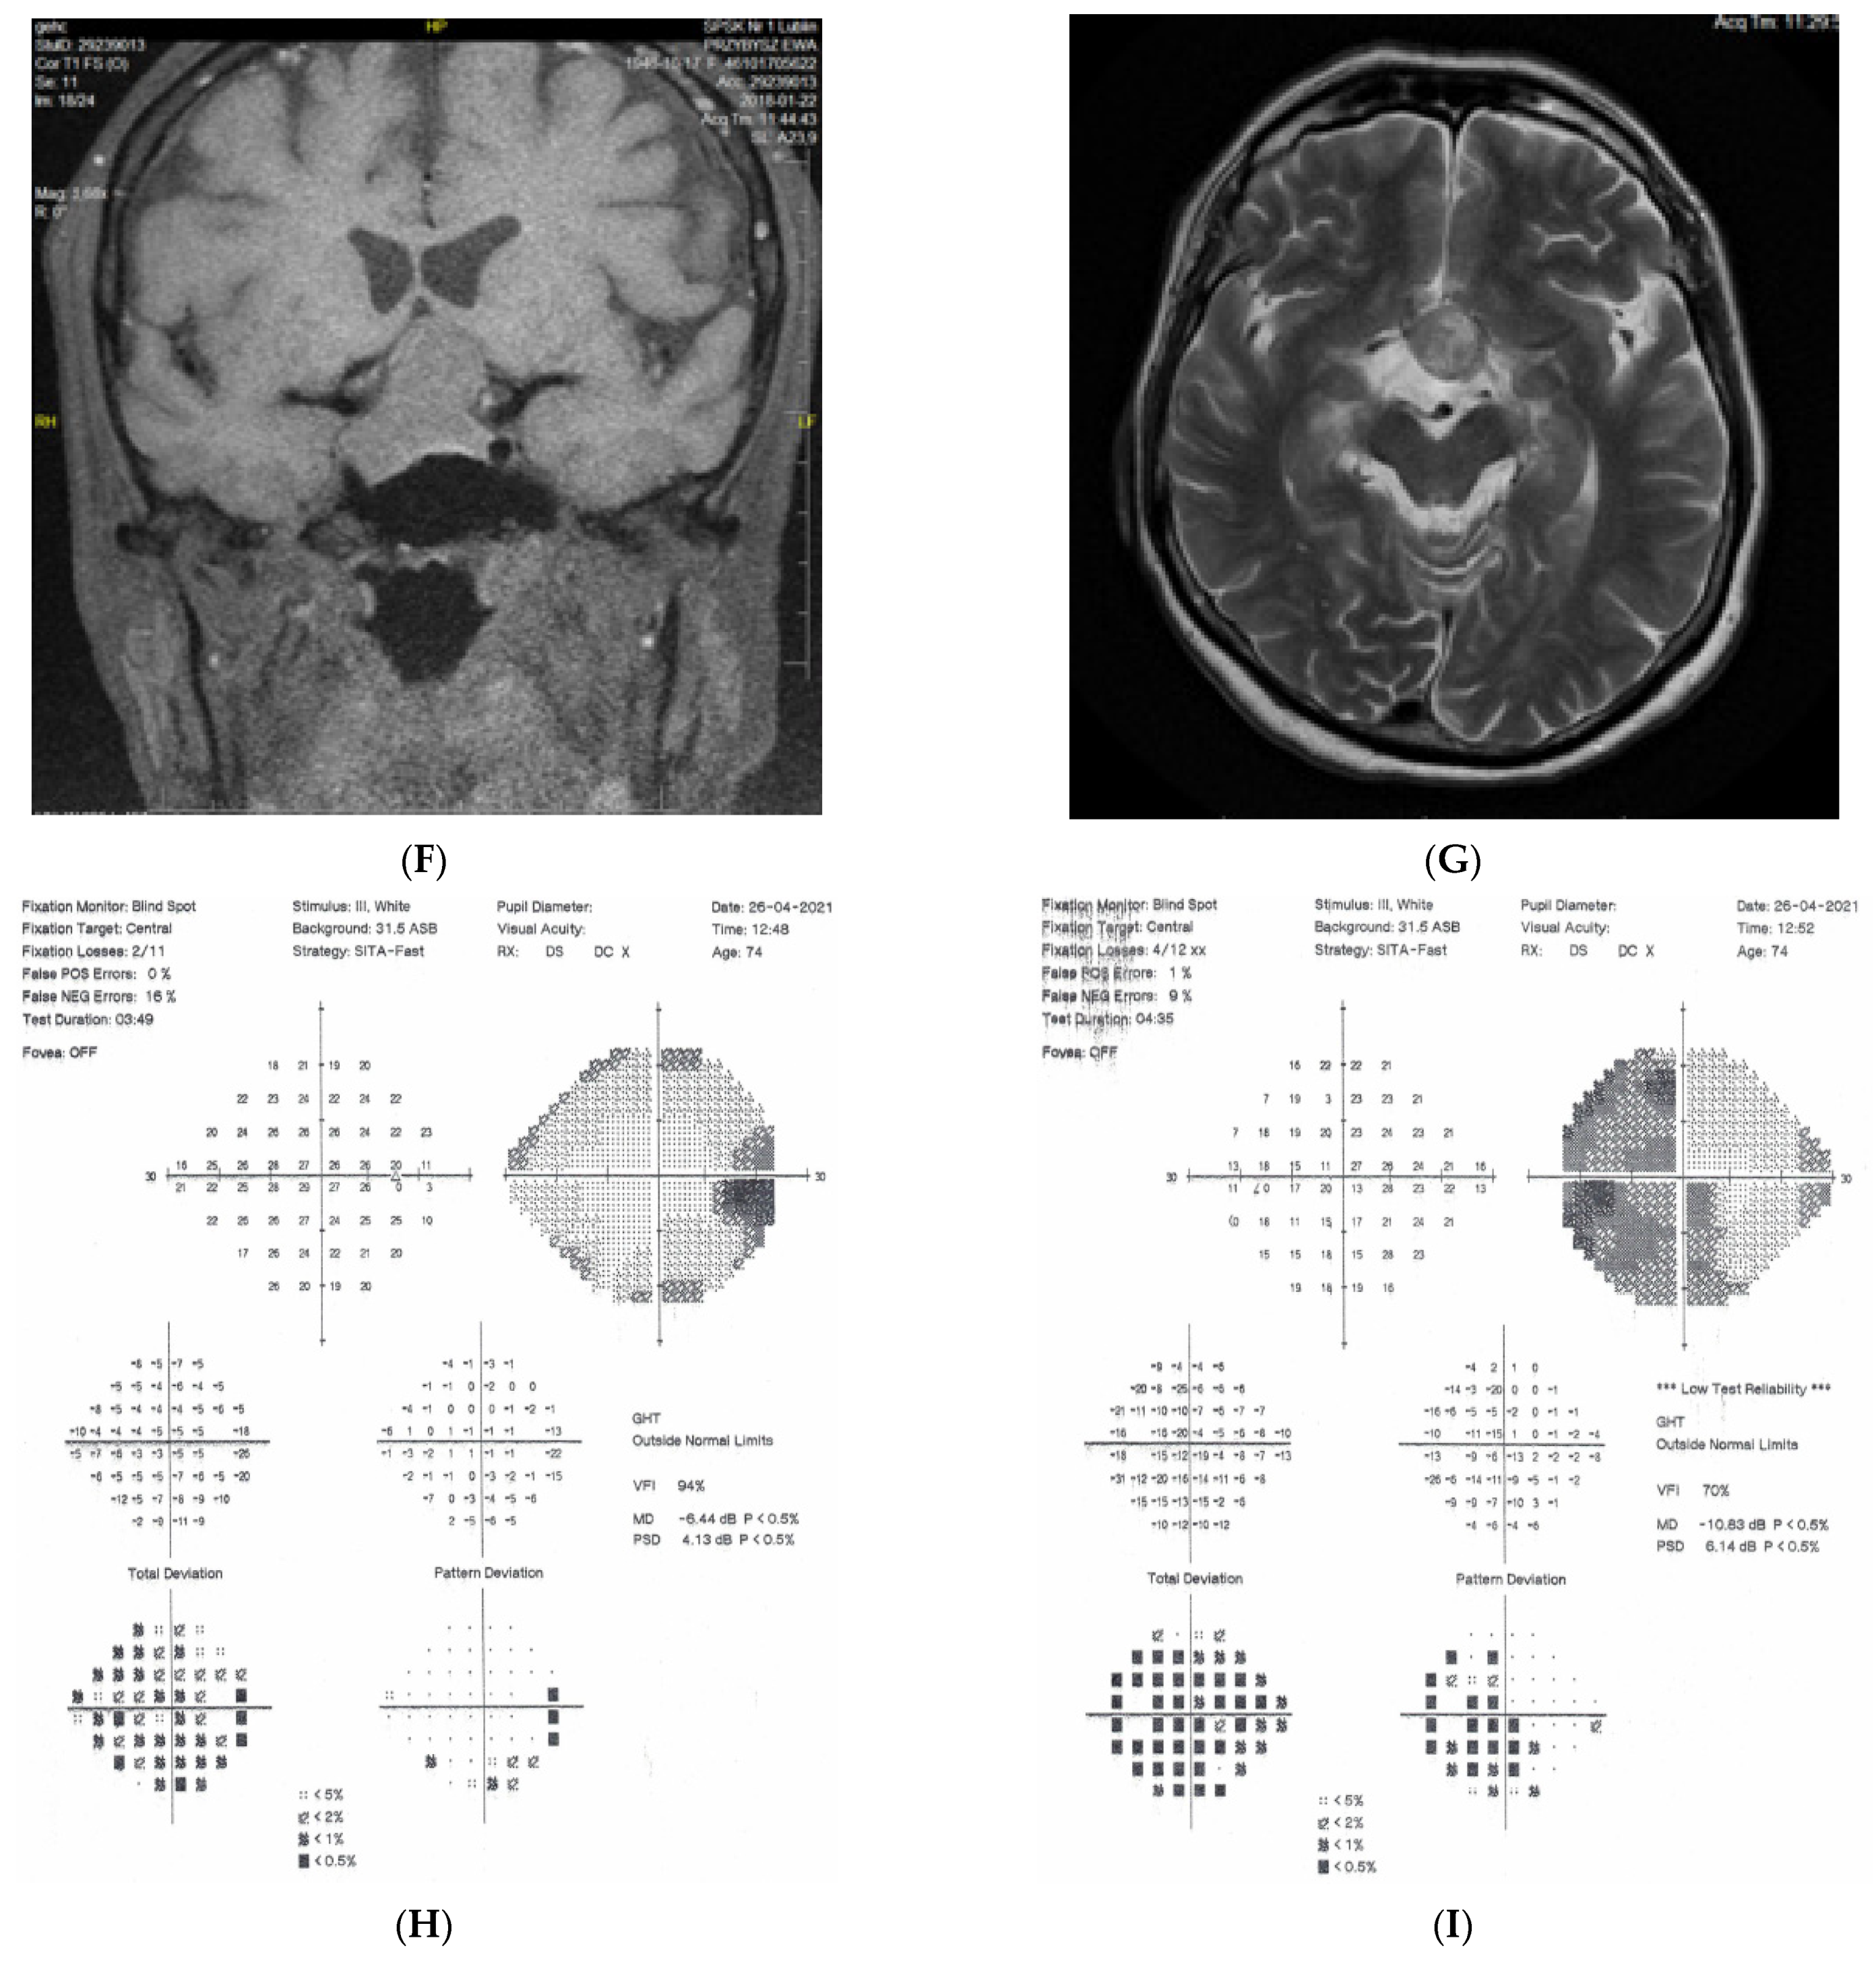

2.2. Case 2

2.3. Case 3

2.4. Case 4

2.5. Case 5

3. Discussion

- Lesions developing in association with an optic nerve develop unilaterally and are characterized by optic disc pallor, VF defects, and OCT findings (their morphology may differ from classical glaucomatous defects).

- Chiasmal lesions develop slowly and frequently, bilaterally but asymmetrically. MR scans usually suggest pituitary adenoma, craniopharyngioma, or olfactory groove meningioma of this region. In almost two thirds of the patients with chiasmal syndrome, this is due to pituitary macroadenomas [7]. Virtually all patients have asymmetrical bilateral visual field loss, majority decreased color vision, half decreased visual acuity, and only one-third optic disc pallor [8].

- It is noteworthy that retrotectal or even retrochiasmal lesions are unlikely to be misdiagnosed as causes of optic neuropathy. Intracranial lesions, if develop rapidly, may evoke intracranial hypertension that will usually be diagnosed promptly as, e.g., papilloedema. If not diagnosed, sooner or later the patient will be referred due to the consequences of raised intracranial pressure or malignancy itself. If the lesion develops slowly, the ophthalmic presentation will be a visual field defect, with respect to the vertical meridian, but pallor does not develop as the lesion is located distal to ganglion cells. In these typical situations when retrotectal areas of visual pathways are involved, a picture of the right or left homonymous hemianopia is present, with normal discs and pupillary reflexes. Such pictures develop in stroke, tumors, and trauma, etc.